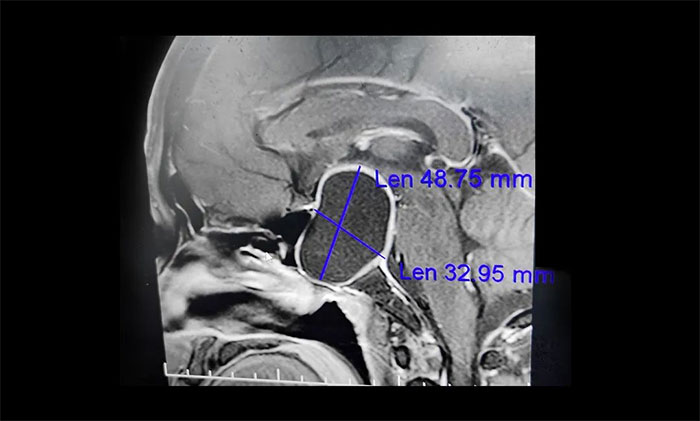

▲垂體大腺瘤伴囊變,壓迫視神經(jīng),導(dǎo)致視野缺損、視力下降

“醫(yī)生,我已經(jīng)做了白內(nèi)障手術(shù),怎么眼睛還是看不清東西呢?”半年多前,67歲宋阿姨的因視力模糊和下降到眼科就診,被確診為右眼白內(nèi)障。當(dāng)?shù)匮劭漆t(yī)生為宋阿姨進(jìn)行了白內(nèi)障手術(shù)。本以為手術(shù)后,視力便可慢慢恢復(fù)正常。誰料,右眼視力卻愈發(fā)“不好使”,左眼的視力也下降明顯。通過對宋阿姨眼睛的復(fù)查,雖然白內(nèi)障得到改善,但患者視力仍很差,雙眼外側(cè)的余光變窄,因此醫(yī)生高度懷疑他視力下降的原因可能跟腦部病有關(guān),因此建議宋阿姨到神經(jīng)內(nèi)科做進(jìn)一步檢查。最終查出4公分大的巨大垂體瘤。